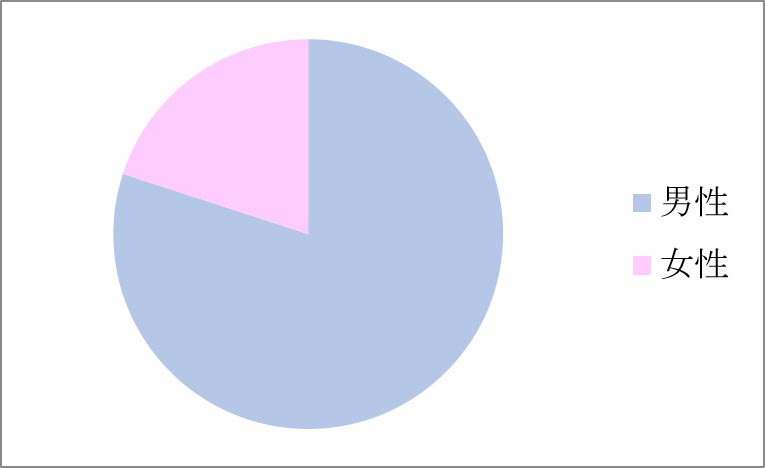

Q. 男女比はどうですか?

A. 15例の性比分布は、下グラフのように男性12例(80%)、女性3例(20%)と男性が多くを占めていす。